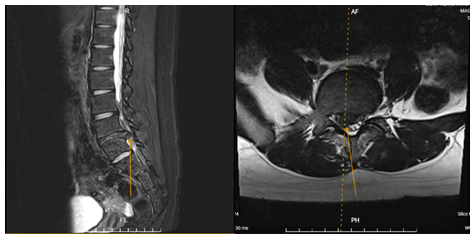

Phim chụp thể hiện vị trí thoát vị của người bệnh B.G.H khi vào viện

Tại Bệnh viện, qua thăm khám lâm sàng kết hợp với các xét nghiệm và chẩn đoán hình ảnh, bác sĩ xác định người bệnh mắc thoát vị đĩa đệm đốt sống thắt lưng L4–L5 lệch phải, gây chèn ép rễ thần kinh. Sau khi hội chẩn, người bệnh được BSCKII Hà Xuân Tài – Trưởng khoa Ngoại Thần kinh trực tiếp phẫu thuật bằng phương pháp nội soi cột sống – một kỹ thuật tiên tiến, ít xâm lấn.